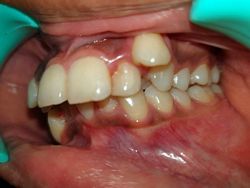

Case No: 22

Malocclusion Type: Class I Malocclusion.

Mechanics: MBT Mechanics.

Treatment: Class I Malocclusion with crowding in upper and lower anteriors treated by Non-extraction (permanent teeth)method.